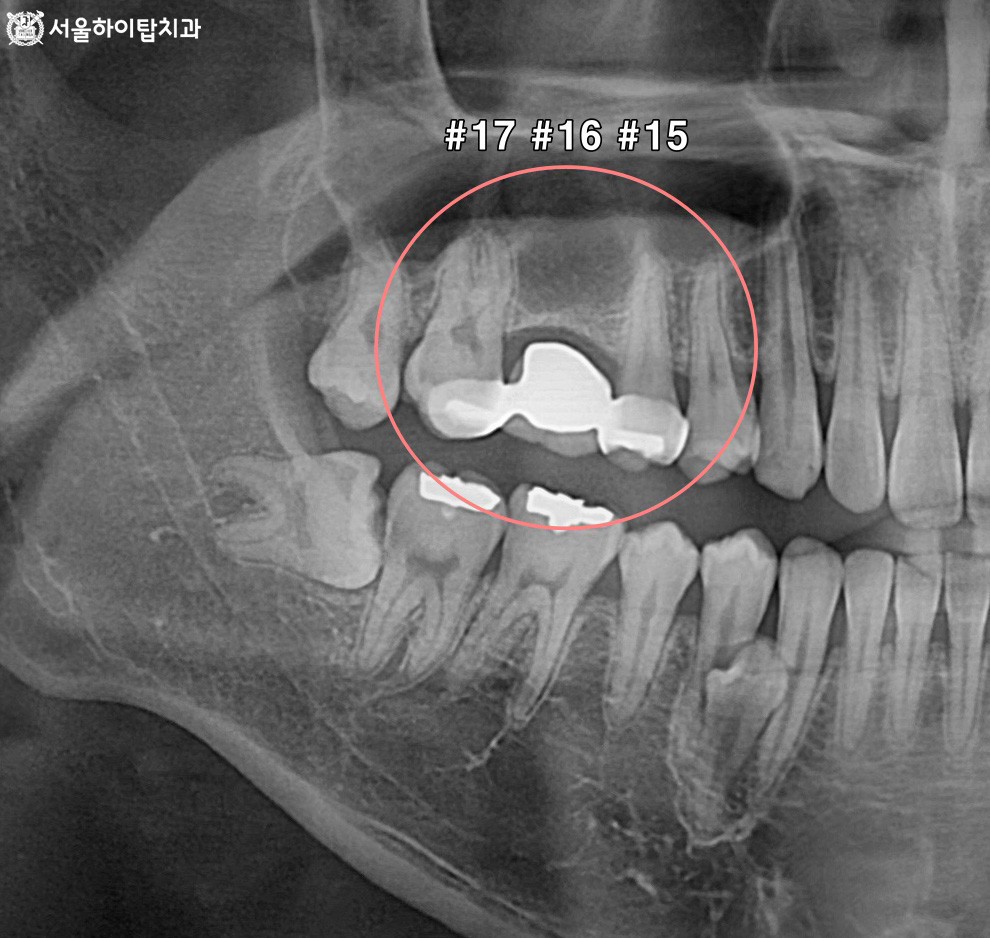

십정동 치과 상실된 치아가 불러오는 연쇄적 문제? 치조골 흡수와 기울어진 어금니, 뼈이식 동반 임플란트 과정 동암역 치과 : 균형 잡힌 저작이 중요한 이유, 전반적으로 손상된 치아 및 잇몸 임플란트를 통해 저작 기능 개선 간석역 치과 치주염으로 인한 치조골 흡수, 치아 파절 및 마모까지 임플란트 가상 시뮬레이션을 통한 안전한 수술 과정 1 2 Next Archives 2026년 4월 2026년 3월 2026년 2월 2026년 1월 2025년 12월 2025년 11월 Categories 미분류 신경치료 심미 치료 임플란트